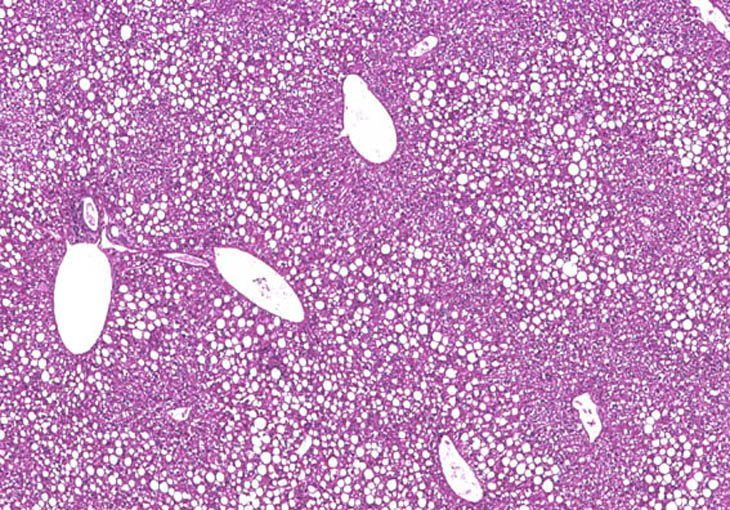

Periportal fatty change. The large, sharply delineated, clear vacuoles represent fat that has been dissolved during tissue processing. Deposition of fat in the hepatocyte cytoplasm often displaces the hepatocyte nucleus to the periphery of the cell.

Large areas of fatty change without a distinct lobular pattern are present in this liver. The large, sharply delineated, clear vacuoles represent macrovesicular fat that has been dissolved during tissue processing. Deposition of fat in the hepatocyte cytoplasm often displaces the hepatocyte nucleus to the periphery of the cell.